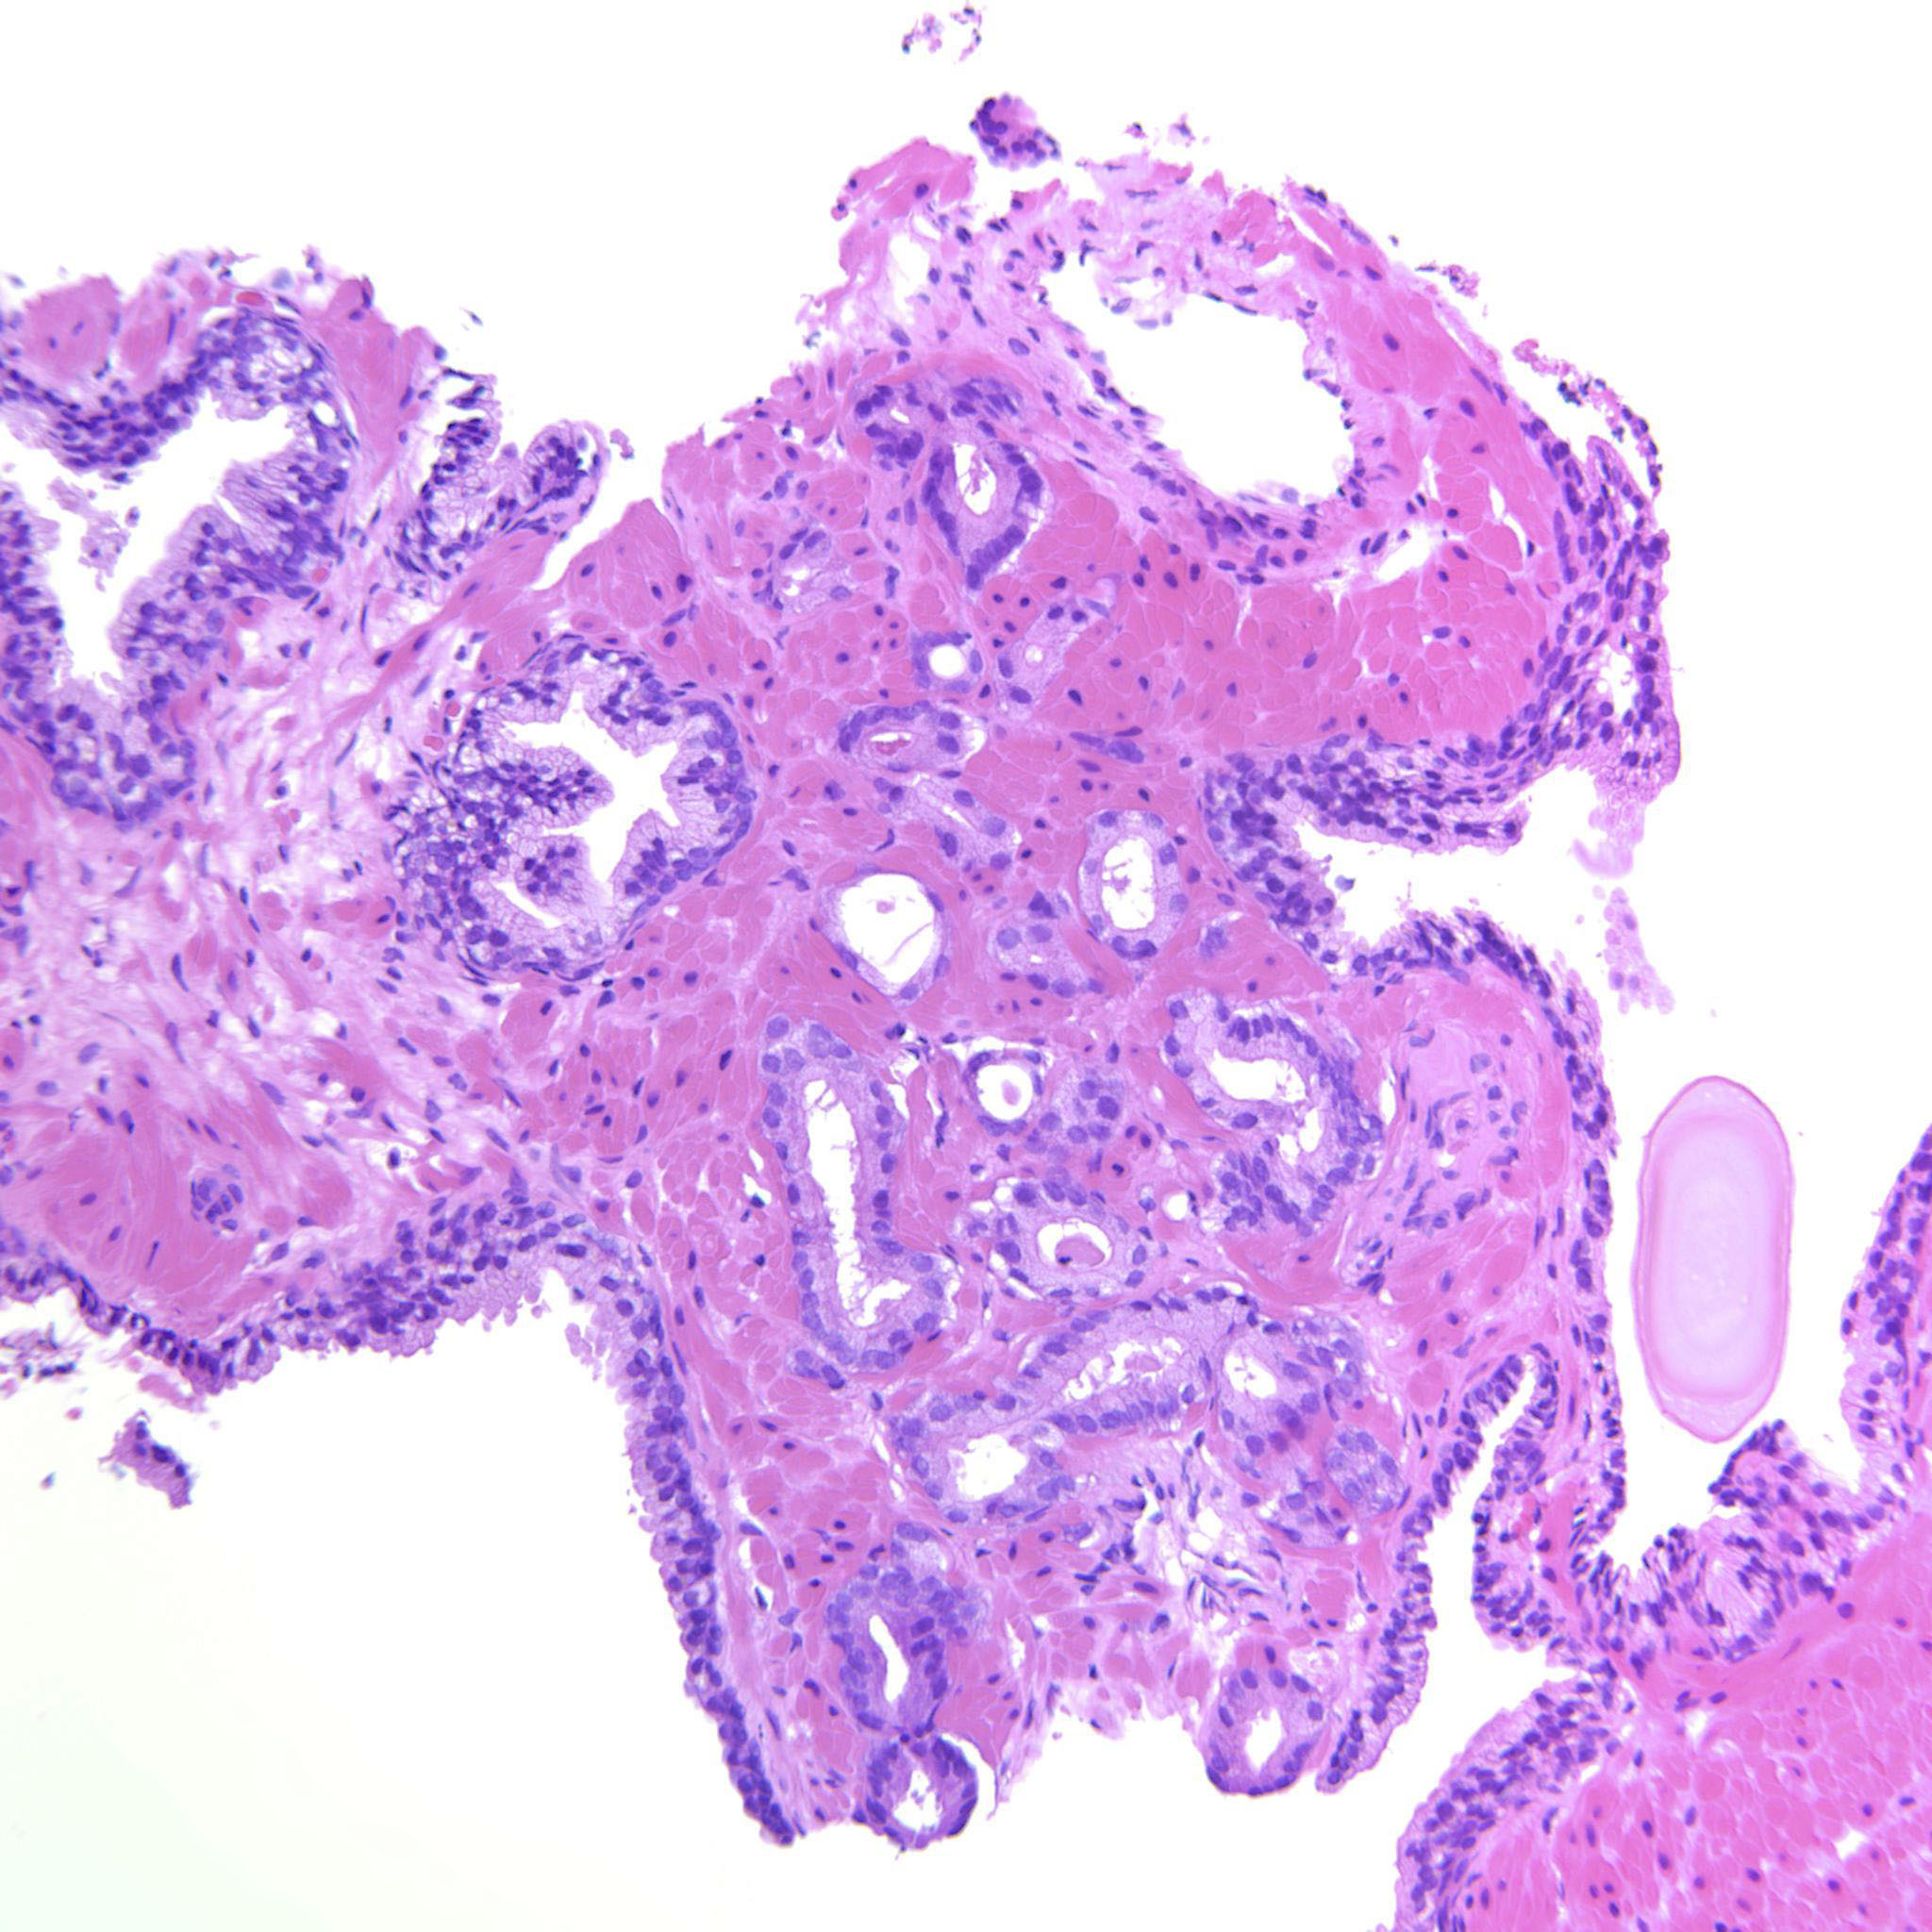

Consensus grade: GS 3+3=6 (ISUP 1)

Case description (by case creator):

A couple of groups of well-formed glands with a few structures that most likely are tangential cuts.